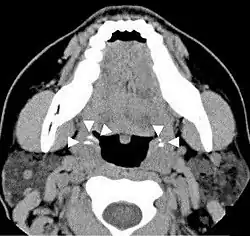

Occasionally there may be pain when swallowing.[13] Even when they are large, some tonsil stones are only discovered incidentally on X-rays or CAT scans. Other symptoms include a metallic taste, throat closing or tightening, coughing fits, itchy throat, and choking.

Imaging diagnostic techniques can identify a radiopaque mass that may be mistaken for foreign bodies, displaced teeth or calcified blood vessels. CT scan may reveal nonspecific calcified images in the tonsillar zone. The differential diagnosis must be established with acute and chronic tonsillitis, tonsillar hypertrophy, peritonsillar abscesses, foreign bodies, phlebolites, ectopic bone or cartilage, lymph nodes, granulomatous lesions or calcification of the stylohyoid ligament in the context of Eagle syndrome (elongated styloid process).[18]

Differential diagnosis of tonsilloliths includes foreign body, calcified granuloma, malignancy, an enlarged temporal styloid process or rarely, isolated bone which is usually derived from embryonic rests originating from the branchial arches.[19]